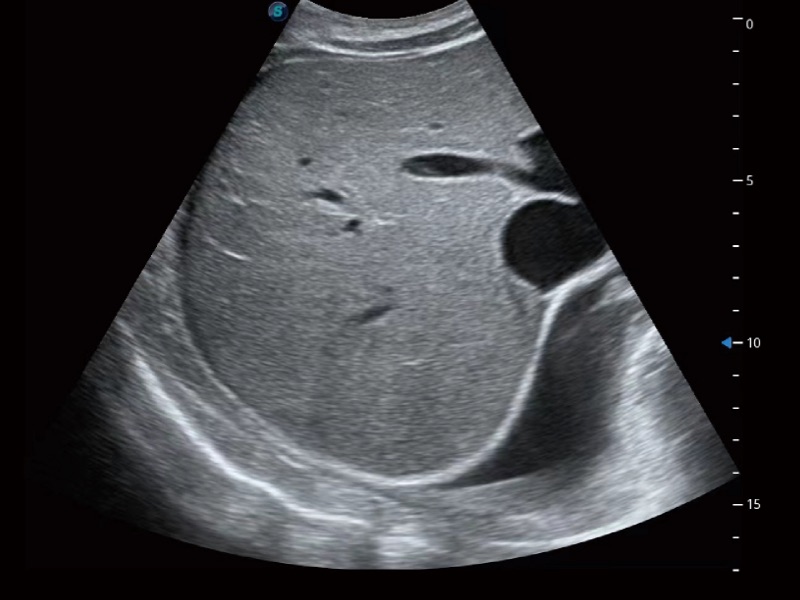

腹部应用

微米成像技术大大提高了器官和病变的可见性。高清对比度分辨率将抑制斑点噪声,同时保持真实的组织结构。

超声检查得益于实时性、经济性、便捷性,目前广泛的应用于临床工作中,超声检查设备已成为帮助临床医生轻松地完成诊断工作的好伙伴。P20 Plus集成了一整套包含了腹部、心血管、小器官、妇产科等全面临床应用功能,轻松应对各种临床问题。